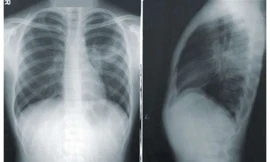

TPO - Dấu hiệu ung thư phổi thường không rõ ràng ở giai đoạn đầu khiến nhiều người chủ quan hoặc nhầm lẫn với bệnh lý hô hấp thông thường. Bệnh diễn tiến nhanh và thường đã di căn khi phát hiện.

TPO - Ung thư phổi là căn bệnh nguy hiểm hàng đầu trên thế giới với hơn 2 triệu người mắc mới và hơn 1 triệu người tử vong mỗi năm. Tại Việt Nam, trong số các bệnh nhân nhập viện, có đến 62,5% không còn khả năng phẫu thuật. Vậy làm thế nào phát hiện sớm bệnh để điều trị hiệu quả nhất?

TPO - Ung thư phổi đang trở thành mối đe dọa nghiêm trọng tại Việt Nam khi mỗi năm ghi nhận hơn 24.000 ca mắc mới và gần 22.600 trường hợp tử vong. Tỉ lệ sống thêm 5 năm chỉ đạt 14,8%, thuộc nhóm thấp nhất trong các loại ung thư phổ biến.

TPO - Tỷ lệ mắc phải của ung thư phổi trong cộng đồng đứng hàng thứ 3 trong các loại ung thư nhưng mức độ nguy hiểm thì ung thư phổi là “sát thủ” hàng đầu gây tử vong cho người bệnh.

TPO - Dấu hiệu sớm của ung thư phổi rất ít xuất hiện và cũng không có xét nghiệm sàng lọc nào có thể phát hiện bệnh ở giai đoạn đầu. Vì vậy, phần lớn bệnh nhân được phát hiện và chẩn đoán khi ung thư đã tiến triển và di căn ra khắp nơi trong cơ thể.